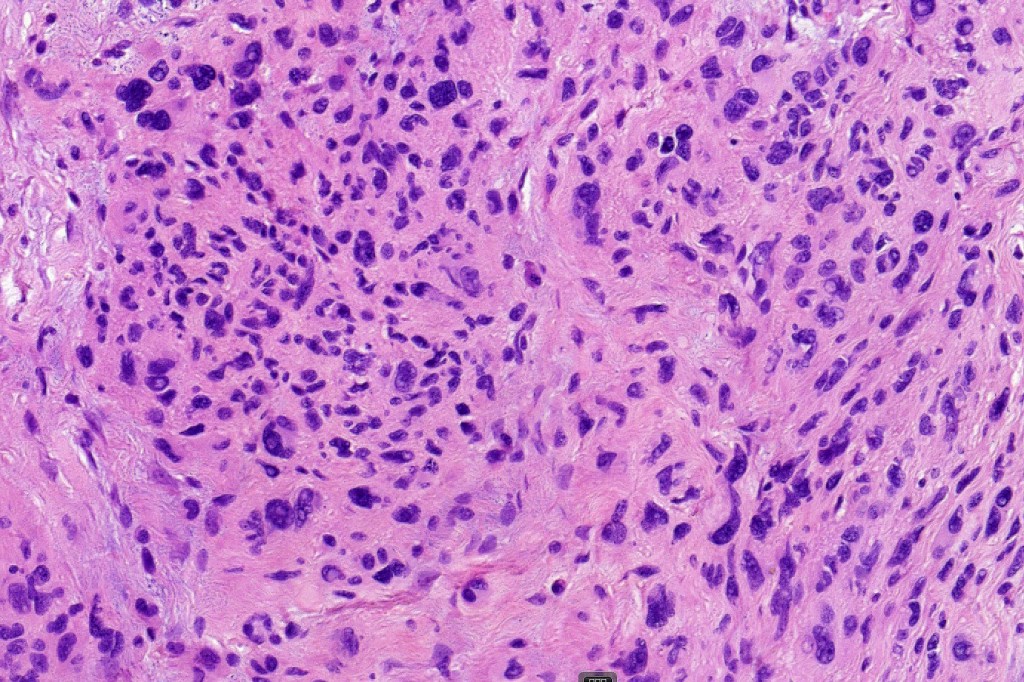

This is a rare variant of melanocytic nevus, so-named because it shares some of the features of ancient schwannoma and not because of its age! It most often arises on the face of older patients as a flesh colored or erthematous nodule. Its importance is that it may be mistaken as melanoma by the unwary.

Histological features

•Mixed cell population- pleomorphic cells (nevoid or Spitzoid)with vesicular or more often intensely hyperchromatic nuclei & often prominent nucleoli, admixed with banal nevus cells, intranuclear cytoplasmic pseudo-inclusions

•Very occasional mitoses may be found